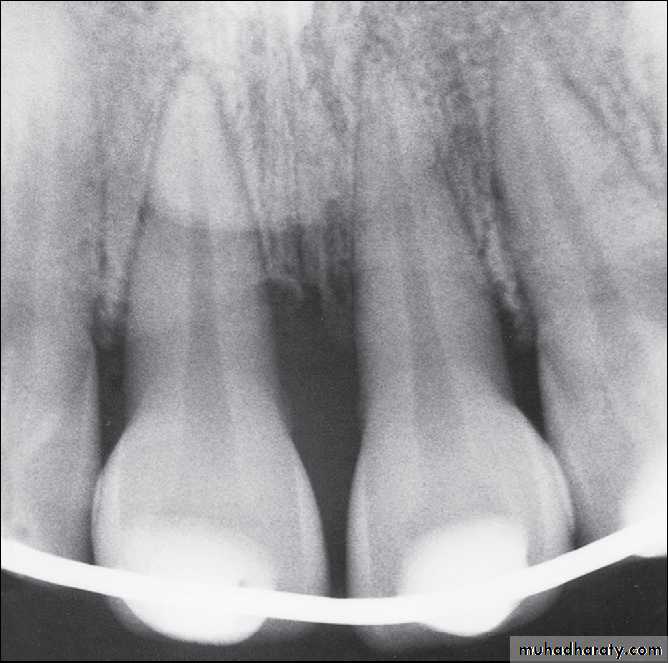

Radiographically widened PDL space at apex of tooth

PDL separated from alveolar bone

- Lateral luxation

Displacement of tooth other than axially (ie, medially, laterally, anteriorly, or posteriorly)

Radiographically, PDL space widened on side of tooth that was displaced away from

Radiographs of extruded tooth before and after repositioning and stabilization with acid-etch composite technique.